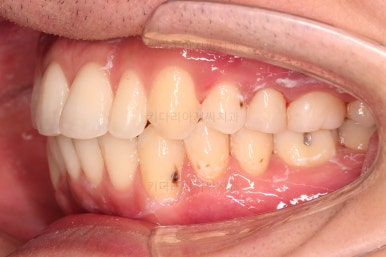

초진 시 입안의 모습입니다.

앞니가 약간 삐뚠 것 말고는 큰 문제는 없어보이네요.